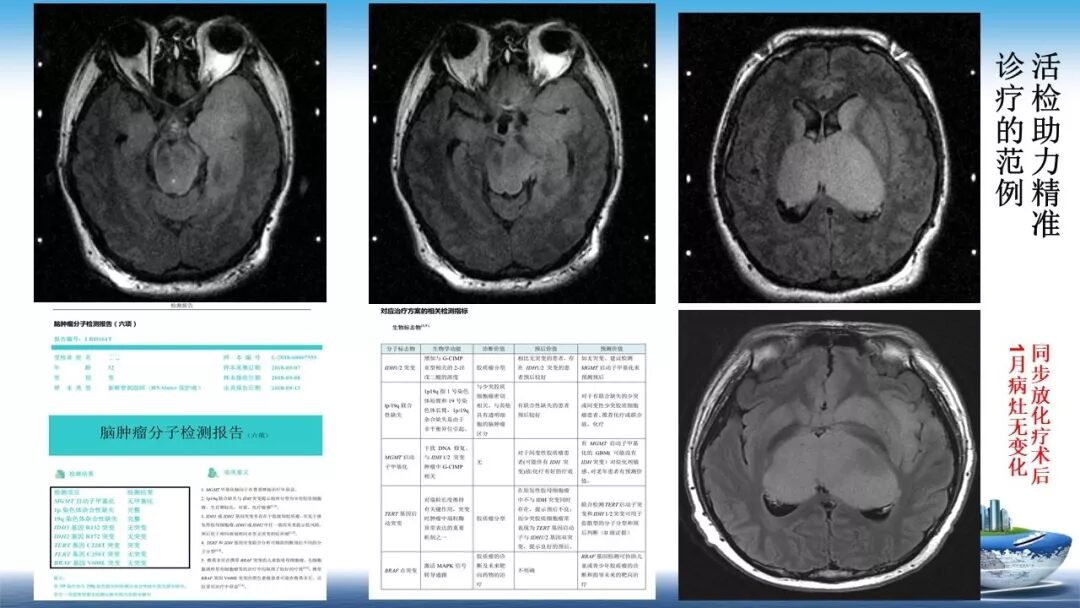

立体定向活检在脑干中线病变精准诊断中的作用

今天为大家带来的是中国人民解放军总医院第六医学中心(原中国人民解放军海军总医院)王亚明、于新、张剑宁带来的精彩课题分享:立体定向活检在脑干中线病变精准诊断中的作用,欢迎观看、阅读!